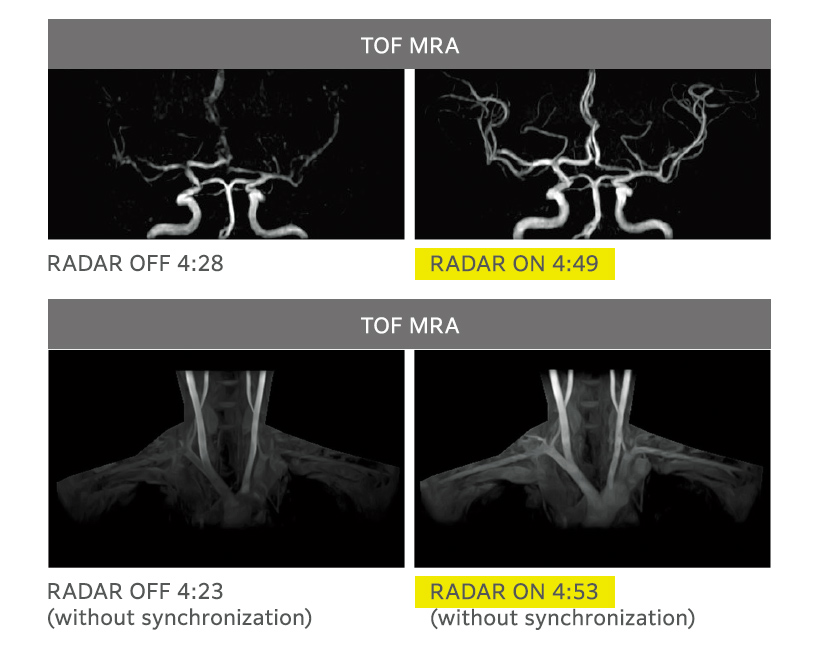

RADAR mitigates motion artifacts enhancing ease of use when imaging with many sequences, all receiver coils, and arbitrary cross-sections. RADAR can be used in combination with highspeed imaging. ECHELON Smart supports TOF and GrE sequences and is compatible with the combined use of RADAR for most of the sequences required for routine head examinations, thus realizing "All Around RADAR."

RADAR has been applied to GrE sequences using a high-precision signal correction technology. This has enabled the combined use of RADAR in all sequences required for routine head examinations.